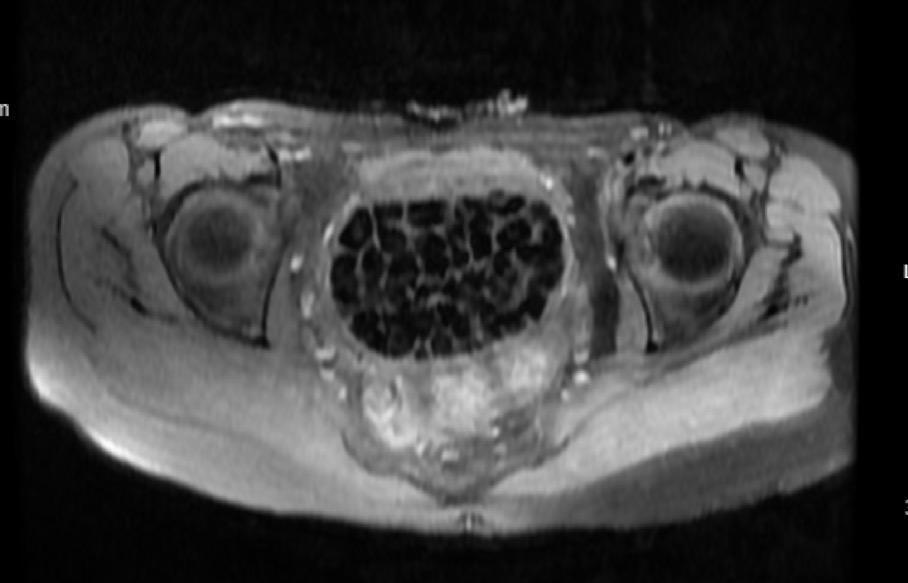

Doğumsal ürolojik hastalıkla dünyaya gelen 21 yaşındaki Fatma Nur Öztürk, şiddetli karın ağrısı şikayetiyle hastaneye gitti, yapılan operasyonla vücudundan 287 adet taş çıkarıldı. Taşlar hem sağlık ekibini hem hasta ve ailesini şok ederken uzmanlar, "Mesaneden vajene ... haberin devamı için tıklayın

VÜCUDUNDAN 287 TANE TAŞ ÇIKARILDI, DOKTORLAR BİLE ŞOK OLDU: "LİTERATÜRDE ÇOK NADİR GÖRÜLEN BİR OLAY" KARIN AĞRISIYLA DOKTORA GİTTİ, VÜCUDUNDAN 287 TANE TAŞ ÇIKARILDI UZMANLAR: "BİZ DE O KADAR TAŞ BEKLEMİYORDUK, ÇOK ŞAŞIRDIK"